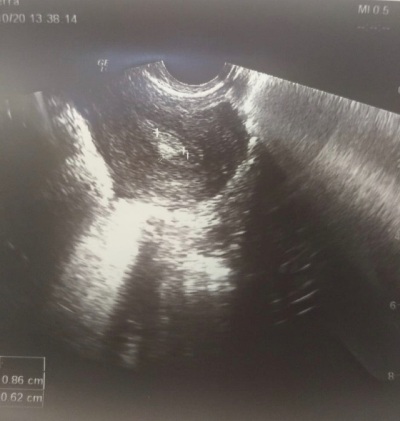

При осмотре выявлено по УЗИ - Эхо-признаки гиперплазии эндометрия. Полип полости матки размерами 9х6 мм.

После контрольного УЗИ м/ таза в 1 фазу м/ цикла полип матки подтвердился. Пациентке проведена успешно гистероскопия и удаление полипа матки под внутривенной седацией.